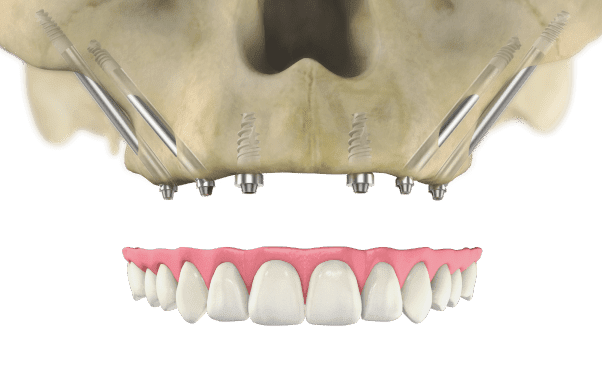

Zygomatic Implants